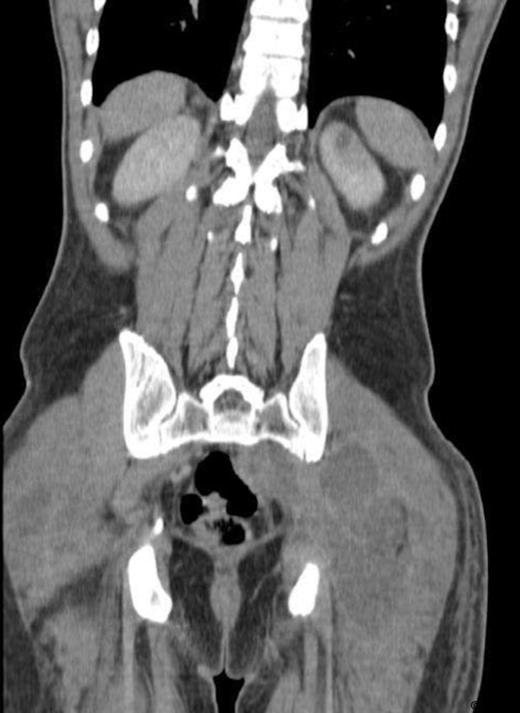

A 31 year old, otherwise healthy young man presented to our emergency department with muscle ache of his legs, a sore throat and fever. Physical examination showed subfebrile temperature, pain of both upper legs and buttocks, but no local inflammation or swelling was noticed. Laboratory examination showed slightly elevated levels of CoReactive Protein (CRP), white blood count (WBC) and Creatine Kinase (CK). The PCR for H1N1 tested positive. With the diagnosis “swine flu” the patient was admitted to the department of internal medicine and therefore oseltamivir treatment was started. However this treatment rendered no success, since the pain increased and spread to both legs and arms. Laboratory findings showed a further increase of both CRP and WBC. The subsequent CT-scan showed multiple abscesses (fig. 1, 2) in the psoas muscle, in both legs and arms. Subsequently 21 abscesses were drained, both surgically and radiologically. All wound and blood cultures showed Staphylococcus aureus, MRSA and PV negative. Our patient was also treated with intravenous flucloxacilline and rifampicine. The patient healed without destruction of muscles.

Diagnosing pyomyositis may be challenging, due to the vague presentation in stage I. Therefore it is often diagnosed with some delay. When the symptoms become more outspoken, apart from history and physical examination, imaging studies are usefull. CT-scan and ultrasound are used to detect abscesses. MRI is the diagnostic tool of choice, because it can detect affected muscles in an early stage. Also more abscesses can be found at unexpected sites, especially when the patient is not responding to treatment. Multifocal abscesses are rare. But, as with our patient, it is of great importance to scan the entire body to detect other abscesses in unexpected regions, if a patient does not respond adequately to the initial treatment.